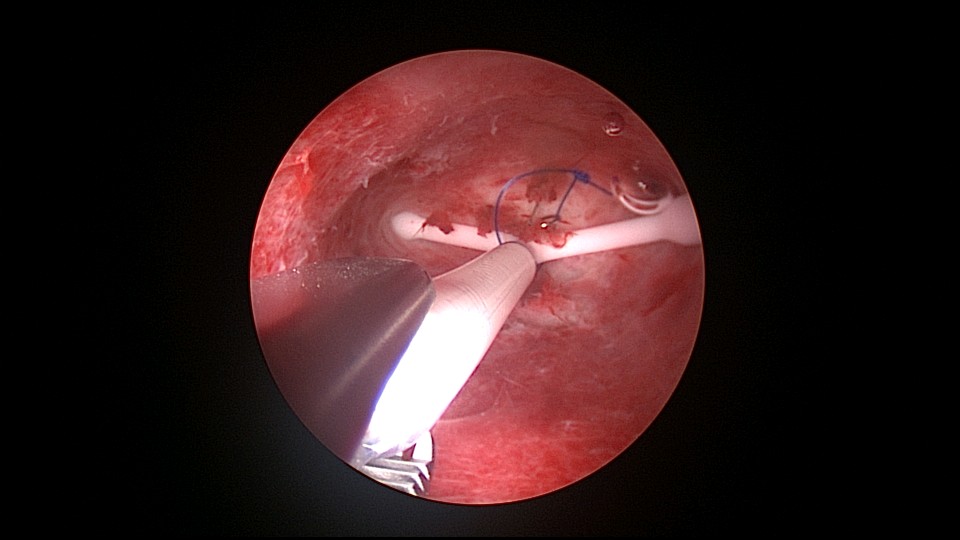

患者39岁,G6P1,顺产1次。2022年5月因输卵管间质部妊娠行宫腹腔镜手术(术前门诊医生诊断宫角妊娠),腹腔镜下行左侧输卵管间质部妊娠套扎开窗取胚术,术中见子宫腺肌症结节明显。2025年3月,严重痛经,皮下注射亮丙瑞林已3个周期,行经第6天,放置曼月乐并固定,拟行缝合固定,宫腔镜下缝合一针,牵拉确认缝合到肌层,推结时缝合处撕裂,拉出曼月乐,立即改为挂钩固定。先将不锈钢挂钩插入宫底肌层,4-0不可吸收线在曼月乐横臂中间套扎形成线圈,将曼月乐置入宫腔,异物钳夹持线圈挂到不锈钢挂钩里,原位固定曼月乐,退出宫腔镜,结束手术。2025年5月复查B超,节育环距宫底3cm,查看图片,线圈较大。节育环距宫底距离跟子宫大小、宫壁厚度、挂钩长度及线圈长度之和有关,保持这个距离不再延长即为手术成功。